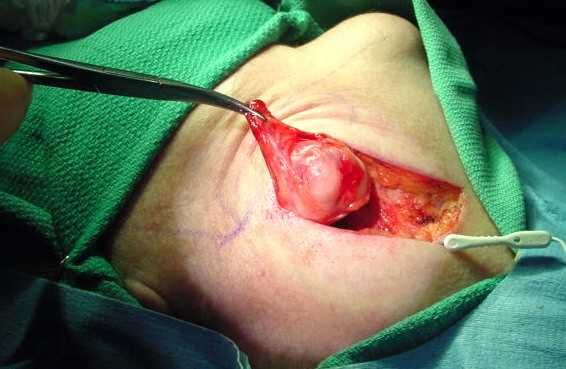

Проведение операции по удалению слюнной железы

При традиционном методе операции пациент принимает положение лежа с запрокинутой и отведенной в сторону головой. Операция предусматривает местную инфильтрационную анестезию. На поднижнечелюстном участке делаются несколько параллельных разрезов, ткани поднимаются, и обнаруживается капсула слюнной железы, которая вскрывается, а ткани железы крайне осторожно извлекаются и удаляются. При срастании злокачественной опухоли с близлежащими тканями последние также удаляются. После этого накладываются швы.

Из поднижнечелюстного протока слюнной камень может удаляться под местным обезболиванием через рассечение слизистой оболочки дна полости рта. Рану после этого зашивают и не дренируют. Иногда требуется экстирпация поднижнечелюстной железы. Такая операция на слюнной железе проводится под общим либо местным наркозом, делается разрез кожи параллельно краю нижней челюсти. Выделяют железу осторожно, учитывая, что рядом находится лицевая артерия. Для профилактики гематомы после зашивания на рану накладывают давящую повязку на 5-6 дней.

Удаление подчелюстных желез

В случаях, когда салиототомия не может использоваться в качестве варианта или если существует реальная масса, следует удалить всю железу. Это достигается за счет сокращения примерно 3 см. под телом нижней челюсти длиной около 4-5 см. Анатомически, сальник готовят путем тщательного лигирования больших сосудов и предотвращения повреждения нервов. Порок обнаруживается и его лигируют. Разрез закрывают пластиковым швом. Весь процесс занимает около 1-2 часов.